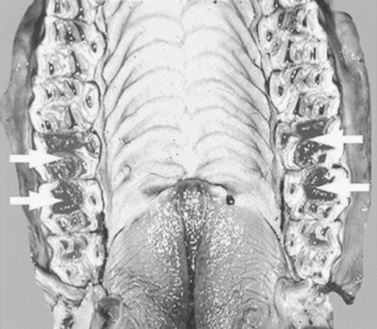

Abdominal radiography is useful to evaluate the small and large intestines for sand accumulation, enterolithiasis, impactions, or small intestinal disorders in foals. When sand is ingested, it generally will accumulate within the large colon along the ventral abdomen8 (Fig. 32-4). Radiography has been found to be a useful method to monitor the resolution of sand impactions after medical management; however, sequential examinations are needed to verify that the volume of sand has reduced.8 If the volume of sand is large enough, it is difficult to determine if an enterolith is present because of summation of the two lesions. Enteroliths are a solid concretion of mineral that usually forms around a nidus, such as a metallic foreign body (Fig. 32-5). The mineral composition is varied, as illustrated by the different opacities present within the enterolith. Radiographs have a 96.4% positive predictive value to detect enteroliths in high-prevalence areas. These enteroliths were generally found to be within the midabdominal radiograph, and 67% of small colon enteroliths caused large colon distention, which was also identified on radiographs.7 Impactions are more difficult to diagnose because usually there is just increased feed accumulation within the abdomen. Although no enterolith or obstruction is identified, granular material can be seen, usually within the ventral colon near the sternal flexure. This is because pelvic flexure impactions will cause the feed material to accumulate orad, causing distention of the left ventral colon (Fig. 32-6). Intestinal disorders such as functional ileus secondary to enteritis (Fig. 32-7) or obstruction secondary to intussusception or meconium impaction (Fig. 32-8) in foals can also be identified on abdominal radiographs. These images show large dilation of the small intestine, and differentiation between functional and mechanical ileus in foals is generally based on the size of the intestine and the volume of gas that is present.9 Evaluation of the abdomen using ultrasound may aid in qualifying the small or large intestinal motility as well as identifying the source of an obstruction if the determination on radiographs cannot be made.

image

Fig. 32-4 Standing lateral radiograph of a 4-year-old Arab mare with a history of colic. Note the large amount of opaque material within the ventral colon, likely secondary to sand accumulation.